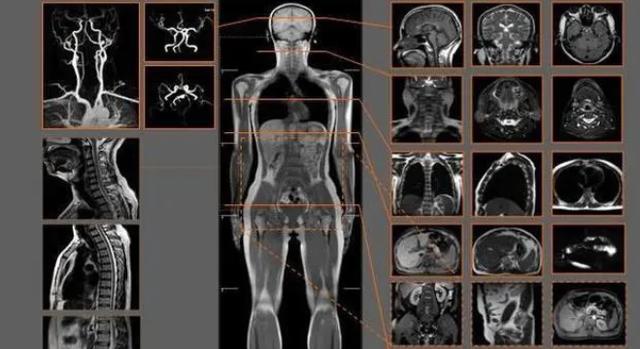

做核磁共振的朋友应该很了解,通常在做核磁共振检查时,有些医生会让患者把身上的首饰,皮带等含铁含金的东西提前摘下来是这些东西不能够带进核磁共振检查室里,一旦患者进入核磁共振检查室里,患者处于一种强大有力量的磁场当中,通过激发患者身体内的氢原子从而进行共振,磁共振的仪器接收到身体里的信号时,便开始工作将数字转化为图像。

对于患者而言,检查身体部位时其他的仪器通常检查时只需要浇一次费用就可以检查出身体的各项问题,磁共振通常检查身体的某一个部位,价格也在500-1000不等,患者如果需要做全身的检查,这一项检查就会花掉大量的金钱,对于一些身体贫困的患者完全没有必要,即使通过核磁共振做了全身的检查,如果在检查后发现身体只会出现一些小的疾病,会给家庭带来一定的负担。

大家做核磁共振检查时通常都会排队,即使一天当中排上了队结果也会在第二天或者第三天才能出。核磁共振检查是属于一项高科技高难度的检查技术,患者在做核磁共振检查时通常耗费的时间过于长,一项简单的核磁共振身体的某个部位进行扫描,也会花上几个小时不等。